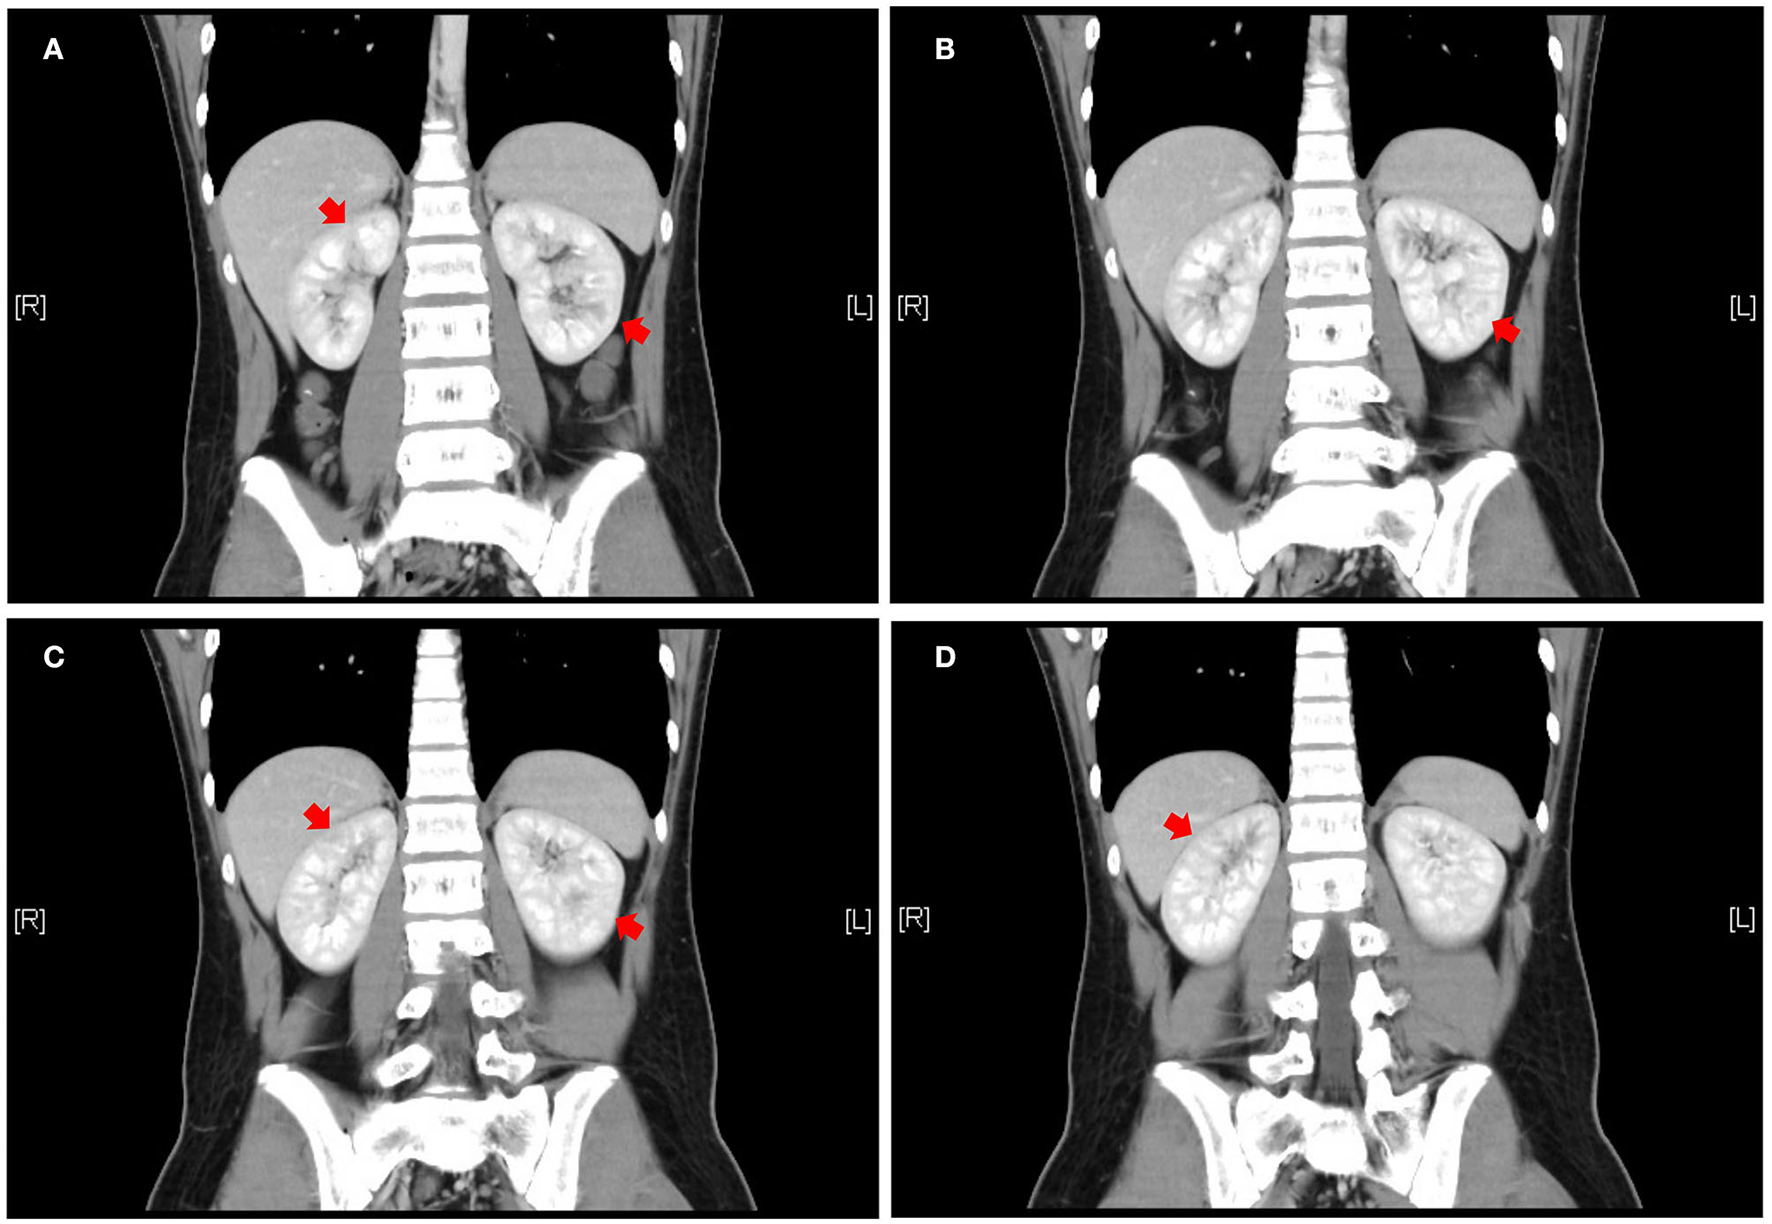

The patient was a 14-year-old boy who had a 5-year history of UC. He was treated with eight doses of infliximab (5 mg/kg) and mesalazine (2 g/day) for 2 years, and he subsequently maintained clinical remission. Two years after mesalazine withdrawal, he was administered mesalazine (2.5 g/day) again owing to relapse. Leukocyturia was found after using mesalazine for 2 months and the patient denied any occurrence of fever, fatigue, nausea, hematuria, or dysuria. Physical examination revealed the following: weight, 65.3 kg; height, 172 cm; body mass index, 22.21 kg/m2; and blood pressure, 111/71 mmHg. No focal abdominal tenderness, rebound, or guarding were found; no edema was observed over his body. Urinalysis of the first-morning urine showed a full field of leukocytes (high power) without hematuria, bacteriuria, glucosuria, or crystalluria. Urine-specific gravity was normal. The urinary protein was 307 mg/L and protein to creatinine ratio (P/C ratio) was 0.23 mg/mg. Serum creatinine was 0.81 mg/dl and cystatin C was 0.91 mg/L. Both aerobic and anaerobic bacteria of urine cultures were negative. Serum electrolytes were normal. Kidney ultrasound did not show evidence of changes in volume, enhancement or decrease in cortical echo, or nephrolithiasis. Renal enhanced computed tomography showed uneven enhancement in both kidneys, with a locally slightly lower enhancement area (Figure 1). In addition, renal biopsy results were normal. The pediatric UC activity index (PUCAI) score was 30. Given that kidney injury may be associated with mesalazine, treatment with mesalazine was discontinued.

Figure 1

Abdominal enhanced CT coronal view, front to rear, numbered A to D. Patchy and slightly less enhanced areas are seen in both kidneys (red arrows). CT = computed tomography to illustrate the meaning of A–D.